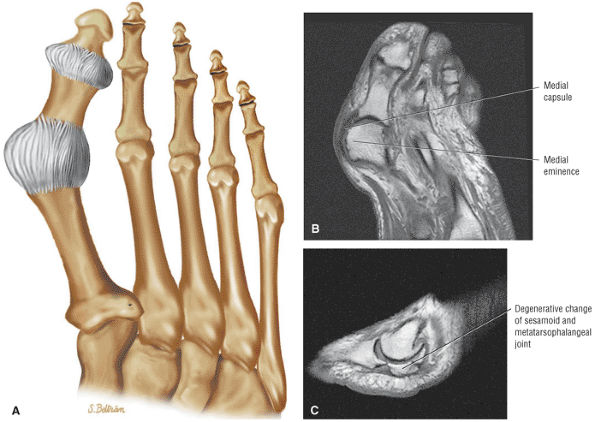

Secondary inflammation of adjacent tendon sheaths

-

Hemorrhage

An empty tendon sheath